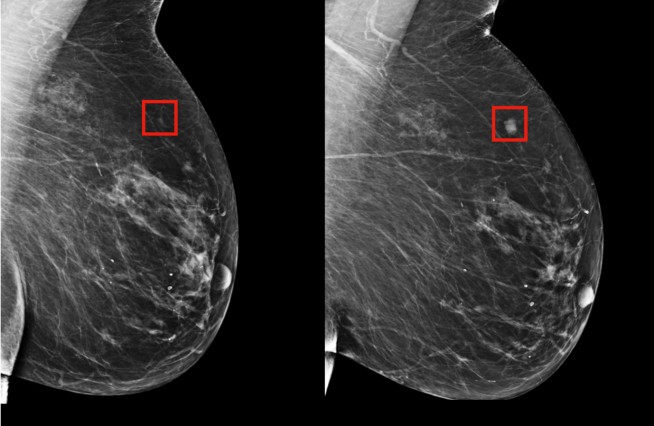

Inteligência artificial prevê câncer de mama cinco anos antes

Foram possíveis de prever 31% dos casos de pacientes de alto risco; antes, só se podiam detectar 18% desses episódios.

Utilizando inteligência artificial (IA), pesquisadores do Instituto de Tecnologia de Massachusetts (MIT) e do Massachusetts General Hospital desenvolveram um modelo para prever o câncer de mama até cinco anos antes de ele se manifestar. Os pesquisadores testaram a tecnologia com dados de 2009 a 2012 provenientes de 90 mil  mamografias de mais de 6 mil pacientes do Massachusetts General Hospital. O sistema de inteligência artificial conseguiu detectar padrões sutis que não podiam ser identificados por humanos nos tecidos mamários, conseguindo antever as chances do desenvolvimento do câncer. A inteligência artificial previu 31% dos casos de pacientes de alto risco, o que é uma melhora significativa na prevenção da doença, uma vez que as técnicas tradicionais anteriores podiam prever apenas 18% desses casos. Os métodos anteriores foram criados com base em dados de mulheres brancas, e um estudo publicado no Journal of Women’s Health mostrou que a eficácia dos testes de prevenção deixava de lado a população negra e hispânica. Por outro lado, agora o modelo criado pela IA foi testado também em mulheres negras, podendo ser mais acessível, embora os testes ainda precisem ser feitos em mulheres indianas e de outras etnias. A tecnologia permitiu ainda conhecer riscos individuais de cada paciente, informações que podem ser usadas para customizar programas de prevenção. Além disso, a mamografia tradicional ainda tem base em faixa etária e o exame recomendado ocorre somente a partir dos 45 anos de idade nos EUA. Com o novo método, isso pode mudar: os pesquisadores dizem que a descoberta pode permitir que no futuro as mamografias possam ser usadas para identificar outros problemas de saúde, como doenças cardiovasculares e outros tipos de câncer. Fonte: Galileu.